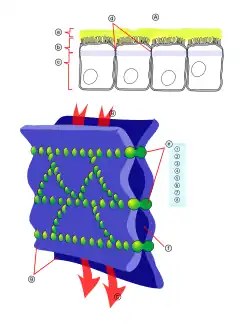

Öffnen der Blut-Hirn-Schranke für therapeutische Zwecke

Das Öffnen der Blut-Hirn-Schranke für therapeutische Zwecke ist, neben den beiden zuvor gezeigten Prinzipien, eine weitere Strategie, um Wirkstoffe dem Gehirn zuzuführen, die normalerweise nicht in der Lage sind die Blut-Hirn-Schranke zu passieren. Das Ziel dieser Verfahren ist eine möglichst reversible Öffnung oder zumindest Lockerung der Tight Junctions, um einen parazellulären Wirkstofftransport in das Gehirn zu ermöglichen. Mit dem zunehmenden Verständnis des molekularen Aufbaus der Blut-Hirn-Schranke – und hierbei vor allem der Tight Junctions – wurden neue Wege und Verfahren zur pharmakologischen, aber auch physikalischen, Öffnung der Blut-Hirn-Schranke entwickelt.[113] Die meisten dieser Verfahren befinden sich noch in der präklinischen Erprobung.

Beim Öffnen der Blut-Hirn-Schranke besteht allgemein die Gefahr, dass für das Gehirn toxische Plasmaproteine eindiffundieren und dann chronische Neuropathologien auslösen können.[114]

Über die Arteria carotis interna werden hyperosmolare Lösungen, beispielsweise von Mannitol oder Arabinose infundiert. Der unterschiedliche osmotische Druck zwischen den Endothelzellen und der infundierten Lösung bewirkt einen Flüssigkeitsverlust in den Endothelzellen, der zu deren Schrumpfung führt. Durch die Schrumpfung entstehen Zugkräfte zwischen den Zellen, was zu einer Öffnung der Tight Junctions und somit zur Öffnung der Blut-Hirn-Schranke führt.[127][128]

Aufgrund des Konzentrationsgradienten zwischen intravasalem und interstitiellem Raum fließt in größerer Menge Wasser aus dem Plasma ins Gehirn zurück (bulk flow). Dadurch werden im Wasser gelöste Moleküle in das Gehirn eingeschwemmt, wobei ein Ödem entsteht.[125][129][130][131][132]

Die durch die Schrumpfung der Endothelzellen bewirkte Öffnung der Tight Junctions beträgt etwa 20 nm.[132] Dadurch können Moleküle mit einem hydrodynamischem Durchmesser von ebenfalls etwa 20 nm in das Gehirn eindiffundieren.[133] Die Öffnung der Blut-Hirn-Schranke ist bei dieser Methode reversibel. Zehn Minuten bis spätestens zwei Stunden nach der Infundierung ist sie wieder vollständig hergestellt.[123][134] Die Einwirkungszeit der hyperosmolaren Lösung beträgt etwa 30 Sekunden. Durch eine Vorbehandlung mit einem Na+/Ca2+-Kanalblocker kann die Öffnungsdauer der Blut-Hirn-Schranke verlängert werden.

Das Verfahren wurde im Tiermodell mit einer Vielzahl von wasserlöslichen Wirkstoffen, Peptiden, Antikörpern, Enzymen und viralen Vektoren für die Gentherapie getestet. Eine Reihe von klinischen Studien zur Therapie von Gehirntumoren in Kombination mit Chemotherapeutika werden in verschiedenen Kliniken durchgeführt.[135] Die Ergebnisse sind für diese Anwendung vielversprechend.[136]